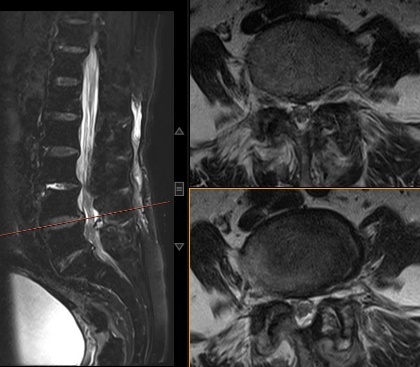

手术非常成功!术后第2天,赵阿姨已经可以下地行走,明显感觉比手术前轻松许多。

术后核磁图片